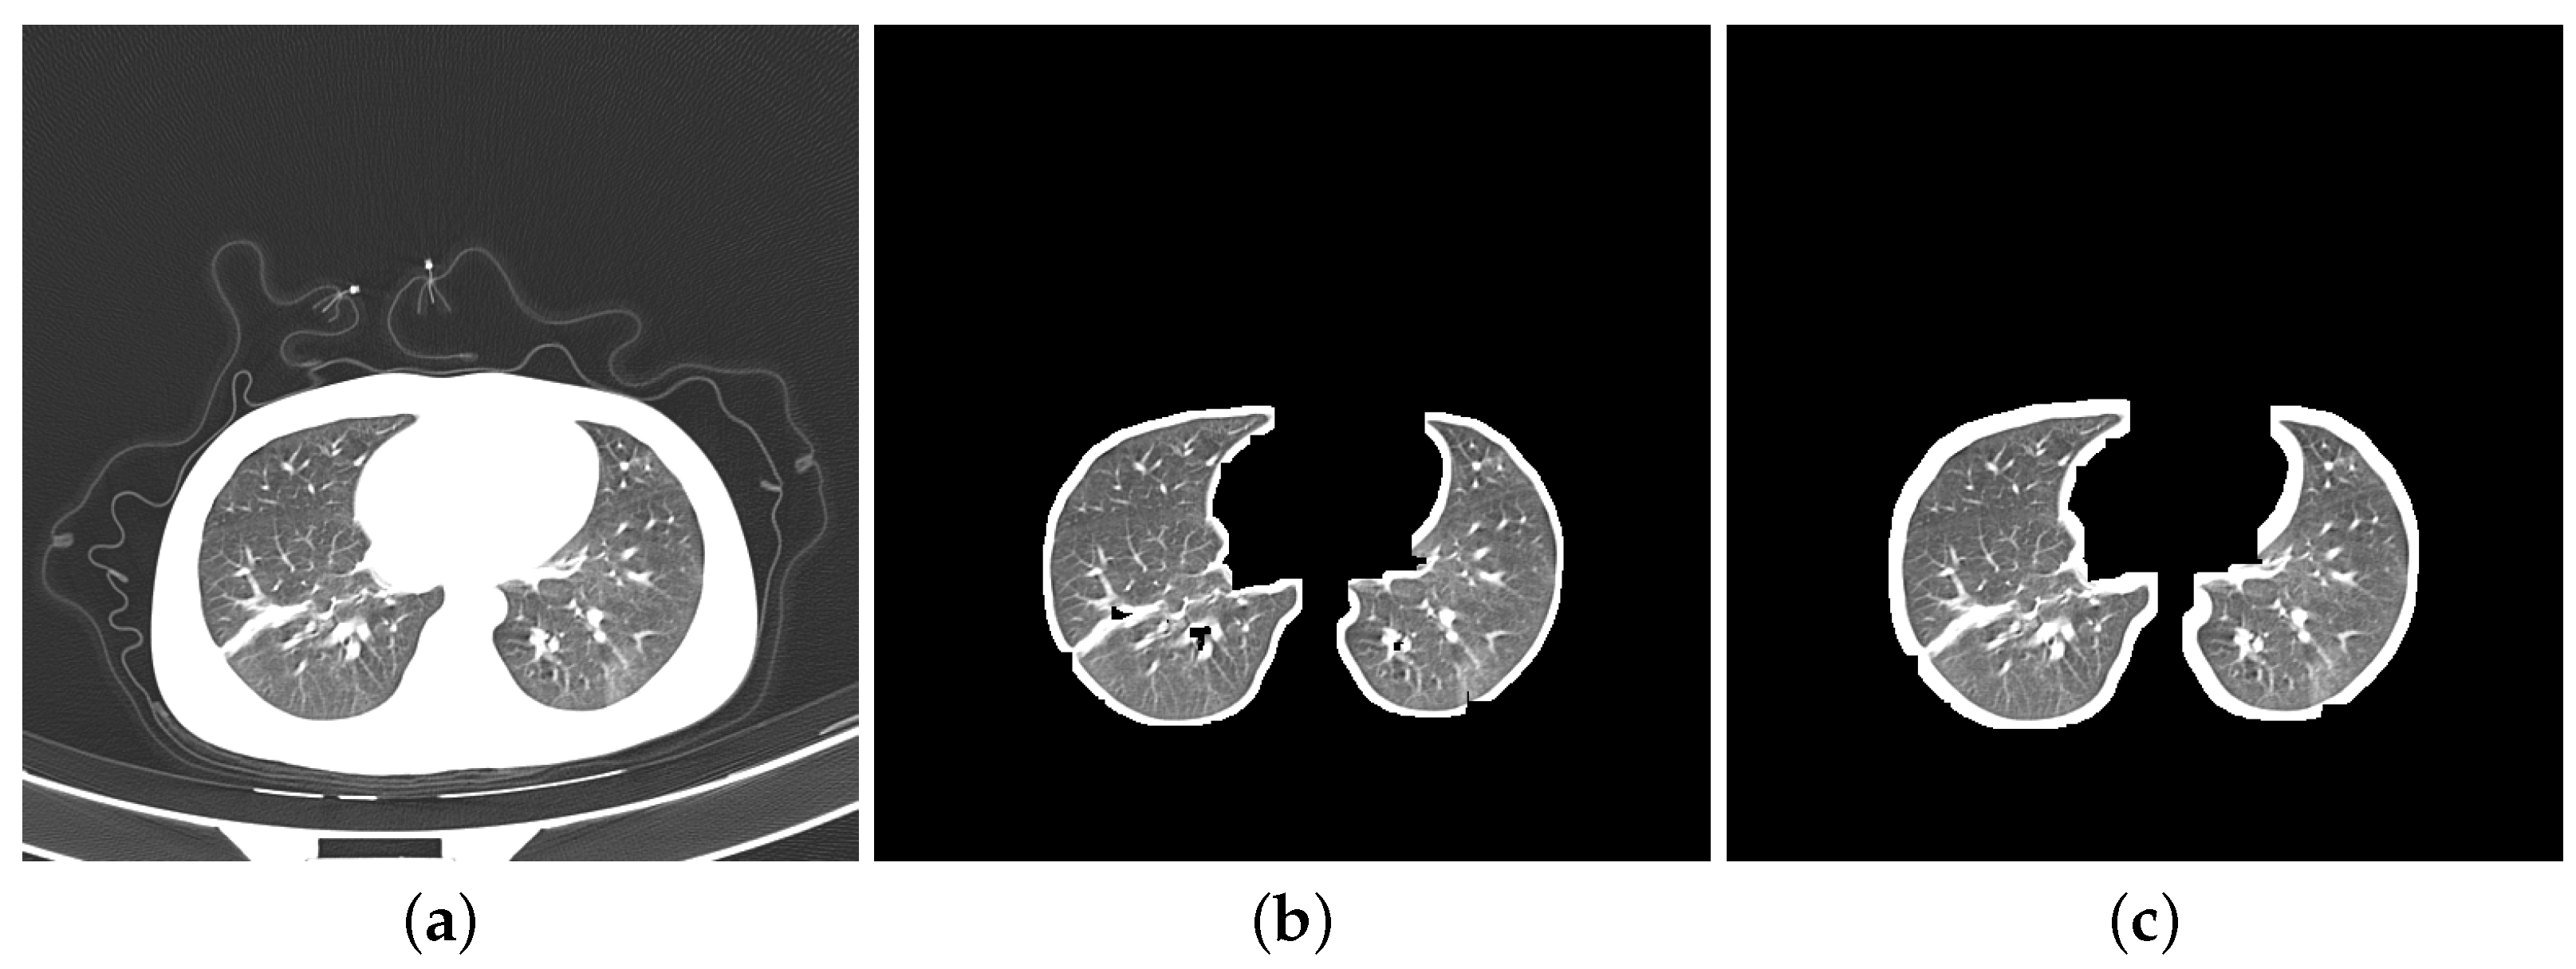

- Segmentation: Segmentation in lung images separates the lung regions from those of the other body parts. More specifically, we segmented DatasetA by using K-Means method to separate lung images from CT slices and eliminate the white background. While the reference paper [20] employed ten dilation kernels, we opted for seven. This choice aimed to achieve a balance between removing the background and preserving the integrity of the lung boundaries. Seven iterations were found to be sufficient for filling small holes within the lungs while minimizing the thickening of the boundaries compared to ten iterations. We did not apply any segmentation to DatasetB as it contains a combination of segmented images from the Clean-CC-CCII dataset and our segmented slices from DatasetA. Figure 2 shows three slices: Figure 2a is from the unsegmented Clean-CC-CCII dataset, Figure 2b is from DatasetA after applying the segmentation using K-Means with seven dilation kernels, and Figure 2c is from DatasetB which is already segmented using K-Means with ten dilation kernels.